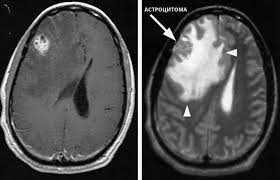

Гигантоклеточные астроцитомы относятся к категории субэпендимарных опухолей. Для выявления патологии первоначальным диагностическим методом является проведение магнитно-резонансной томографии. В ходе обследования образование проявляется солидной размерностью, нечеткими очертаниями. При компьютерной томографии выявляются симметричные кальцинаты согласно проекции на зрительные бугры. Единственный эффективный способ лечения патологии – тотальная резекция пораженного участка.

- Магнитно-резонансную томографию;

- Компьютерную томографию;